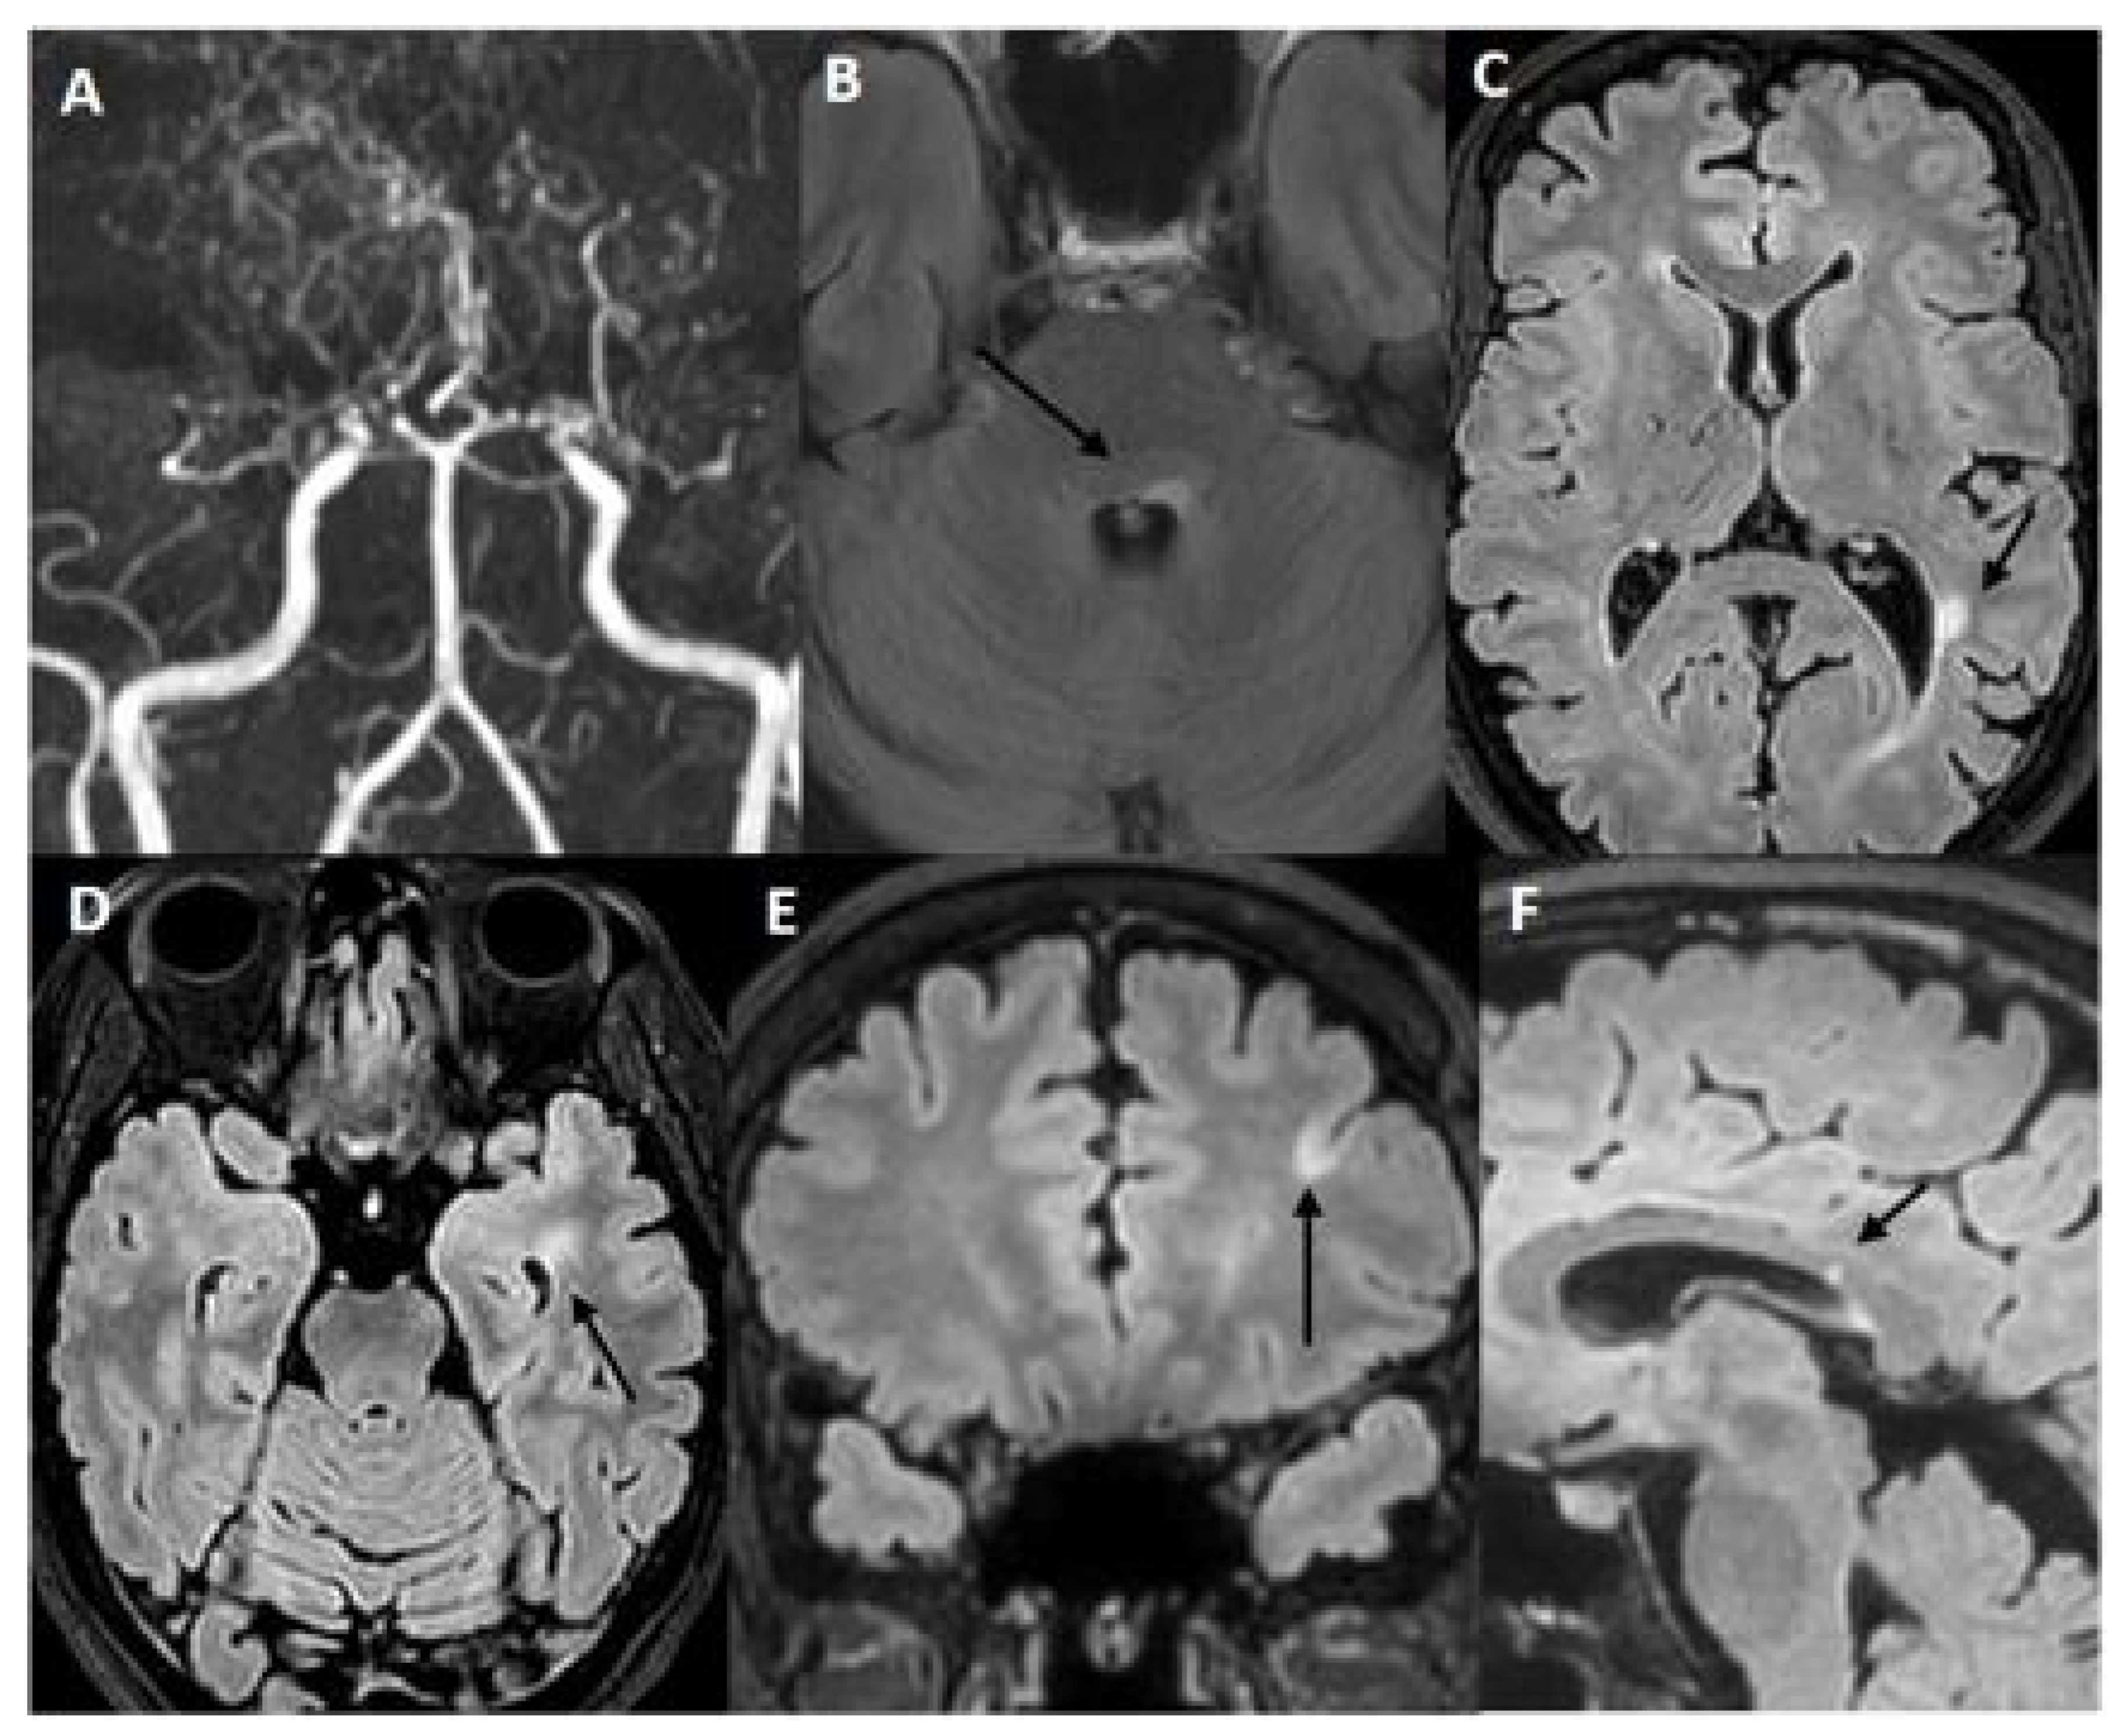

2.1. Case 1: A 45-Year-Old Woman Was Referred to Our Cerebrovascular Department for MMA

| Our Case 1 | Italy/ Caucasian | 45/F | Blurred vision and diplopia | Bilateral brainstem, left frontal and temporal lobe, right temporal lobe, cerebellar hemispheres, left periventricular region | Brain: | − | + | − | AntiAQP4 (−) Anti-ds DNA (+ 1:20) ANA-ENA-ANCA-Anti cardiolipin and beta2GP (−) | Bilateral MCAs and ACAs narrow, thick network of collateral vessels | MMA + MS | TIA | By-pass surgery, Aspirin | Corticosteroids Teriflunomide | 4 years |